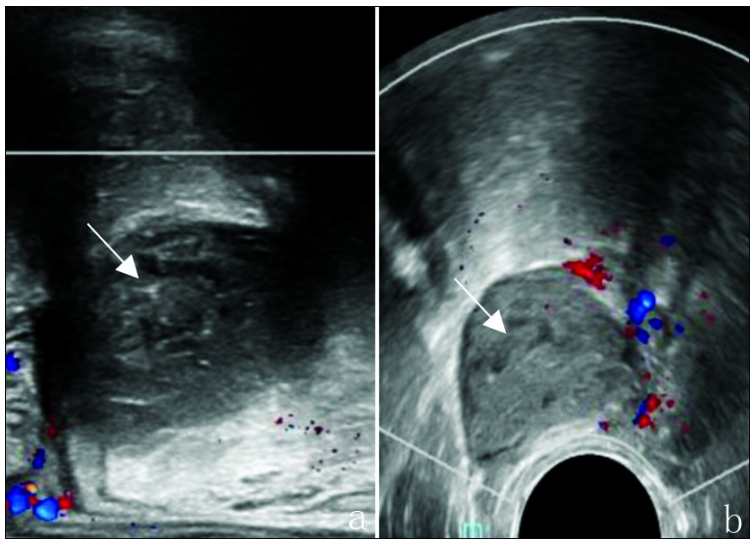

患者男性,60岁,以“肛门疼痛半年,加重1个月”入院。患者一般情况良好。专科检查:直肠后壁触及大小约3.0 cm×2.0 cm肿胀包块,收缩有力。经直肠双平面超声显示直肠后壁与骶骨间见大小约2.7 cm×1.9 cm低回声包块(图1a),界清晰,形态规则,内部未探及血流(图1b)。超声造影显示包块内未见造影剂灌注(图2),结合上述特征性表现,超声诊断为骶前囊性肿物(表皮样囊肿可能)。

图1 骶前表皮样囊肿声像图。a.经直肠线阵探头可见直肠后壁与骶骨间见一低回声包块(箭头所示);b.经直肠凸阵探头可见包块内部无血流信号,包块包膜光滑完整(箭头所示)。